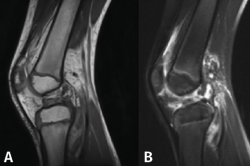

Figura 4. Técnica transepifisaria o todo epifisaria.

Figura 5. Radiografía de control intraoperatoria de un paciente de 6 años con reconstrucción según la técnica transepifisaria de Anderson.

Otra de las técnicas de ahorro fisario es la llamada all epiphyseal. La primera de estas técnicas fue descrita por Anderson(13)(Figura 4) y está indicada en pacientes en estadio de Tanner I, II o III. Se realiza evitando la invasión de la fisis por parte de los túneles, utilizando injerto cuadrifascicular de isquiotibiales, que son estabilizados en el fémur mediante un sistema de tenosuspensión cortical y en la tibia con un tornillo interferencial distal a la fisis (Figura 5). Los resultados en un grupo de 12 pacientes fueron buenos, pero refieren que la técnica es compleja y demandante para un cirujano no experto en rodilla. Esta técnica minimiza el daño fisario, es anatómica y reproduce la isométrica(71). Se ha descrito la aparición de una deformidad angular relacionada con una epifisiodesis secundaria por sobretensionado de la plastia. En la actualidad, se han descrito multitud de modificaciones de esta técnica(15,72,73,74)(Figura 6).